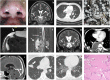

Background: Cryptococcosis is a potentially life-threatening fungal disease caused by encapsulated yeasts of the genus Cryptococcus, mostly C. neoformans or C. gattii. Cryptococcal meningitis is the most frequent clinical manifestation in humans. Neutralizing autoantibodies (auto-Abs) against granulocyte-macrophage colony-stimulating factor (GM-CSF) have recently been discovered in otherwise healthy adult patients with cryptococcal meningitis, mostly caused by C. gattii. We hypothesized that three Colombian patients with cryptococcal meningitis caused by C. neoformans in two of them would carry high plasma levels of neutralizing auto-Abs against GM-CSF.

Methods: We reviewed medical and laboratory records, performed immunological evaluations, and tested for anti-cytokine auto-Abs three previously healthy HIV-negative adults with disseminated cryptococcosis.

Results: Peripheral blood leukocyte subset levels and serum immunoglobulin concentrations were within the normal ranges. We detected high levels of neutralizing auto-Abs against GM-CSF in the plasma of all three patients.